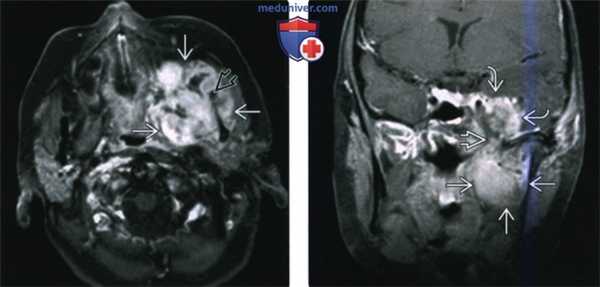

(Слева) МРТ Т1ВИ в аксиальной проекции. Саркома Юинга, локализующаяся в жевательном пространстве. Обратите внимание, что сигнал относительно здоровых мышц гиперинтенсивный. Нижняя челюсть разрушена, определяется лишь небольшой ее фрагмент. Жировая клетчатка окологлоточного пространства смещена в медиальную сторону.

(Справа) МРТ Т2ВИ FS, аксиальная проекция, тот же пациент. Неоднородный сигнал высокой интенсивности. Крупный лимфоузел в заглоточном пространстве слева представляет собой случайную находку.

(Слева) На аксиальной МРТ (Т1ВИ) в жевательном пространстве визуализируется саркома Юинга в виде огромного объемного образования с гиперинтенсивным относительно мышц сигналом. Ветвь нижней челюсти разрушена, на этом изображении виден лишь ее мелкий фрагмент. Полоска окологлоточного жира смещена кнутри.

(Справа) На аксиальной МРТ (Т2ВИ FS) у этого же пациента определяется неоднородный сигнал крайне высокой интенсивности в опухоли. Хорошо различимый заглоточный лимфоузел слева является случайной находкой.